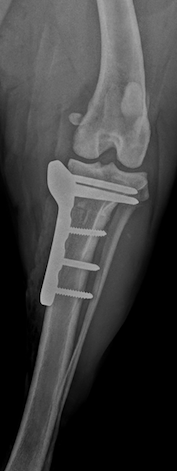

Pickle had a TPLO surgery performed the next day which went well. This involves cutting a circular section off the top of the tibia (shin bone) and rotating it to flatten the joint surface – this stabilises the joint when weightbearing and stops the discomfort caused by cruciate ligament rupture. The cut section of bone is held in its new position with a metal plate and screws until it heals – this takes 2-3 months in total. Jenna had been a little worried that Pickle’s age would count against him, but I reassured her that I have performed cruciate surgery in many dogs of a similar age and their outcomes are almost identical to that of younger dogs. Once the 2-3 month recovery period is over, most dogs return to full function, running on the beach, jumping onto the sofa (if allowed!) and having normal levels of exercise. I haven’t yet had an owner of an older dog regret going ahead with the surgery.